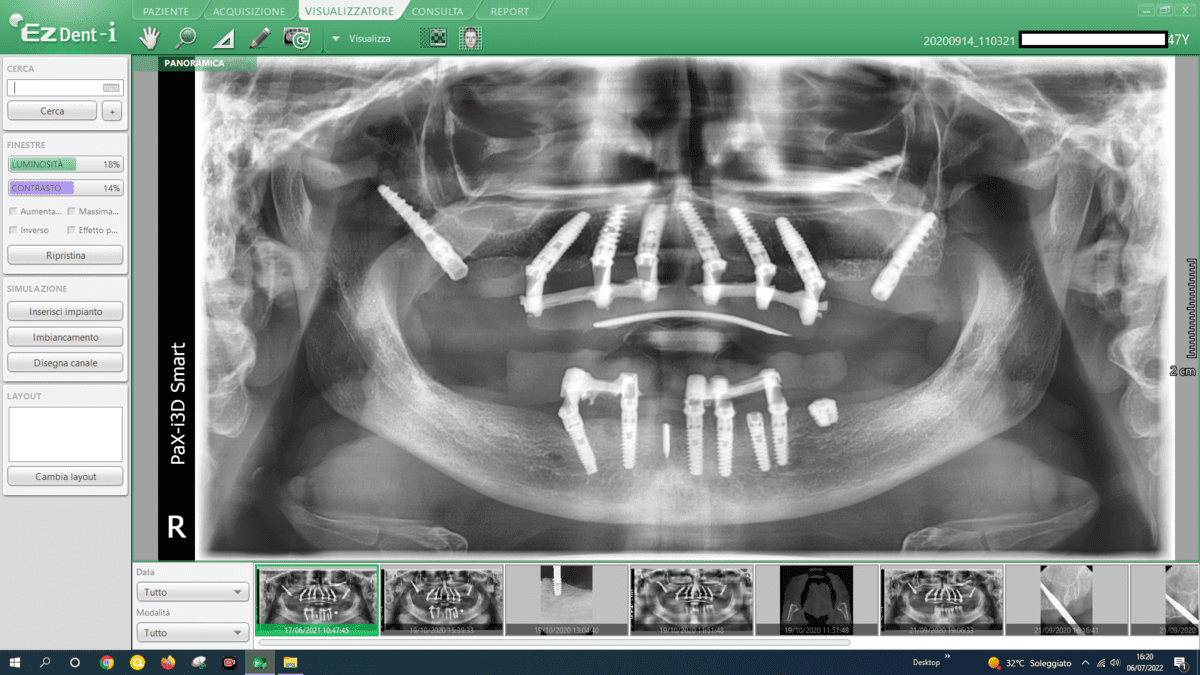

- Advanced Implant Techniques:

- Advanced implant techniques, such as Galileus Cerclage Sinus® mentioned in previous conversations, can offer innovative solutions for addressing atrophies. These techniques focus on strategically placing implants to optimize bone utilization.

In addressing mandibular atrophies, our approach revolves around utilizing advanced implant techniques that offer superior outcomes compared to traditional methods like autologous bone grafts. Here’s a breakdown of our considerations:

- Transverse Implants:

- We employ transverse implants, strategically placed across the mandible. This technique provides stability and support, avoiding the need for extensive bone grafting.

- Blade Implants:

- Blade implants are another key component of our approach. These implants are designed for efficient insertion, providing secure anchorage in atrophic areas without the challenges associated with autologous bone grafts.

- Grid-Like Subperiosteal Implants:

- Our practice utilizes subperiosteal implants configured in a grid-like pattern. This innovative approach optimizes bone contact, ensuring a strong foundation for the implants. This technique eliminates the necessity for autologous bone grafts and their associated complexities.

- Split Crest Procedures:

- Split crest procedures are implemented to widen the alveolar ridge, creating space for implant placement. This technique enhances bone volume and facilitates the successful integration of implants, avoiding the need for time-consuming autologous bone grafts.

- Avoidance of Autologous Bone Grafts:

- We intentionally steer clear of autologous bone grafts due to their drawbacks, including extended surgical procedures, heightened pain levels, and potential complications. Our chosen techniques are not only more efficient but also offer predictability, minimizing the risk of infections and ensuring a smoother recovery.

By embracing these advanced implant techniques, we prioritize patient comfort, reduce procedural complexities, and enhance the overall success and predictability of the treatment. Our commitment lies in providing innovative solutions that not only address mandibular atrophies effectively but also offer a more streamlined and reliable alternative to traditional approaches.